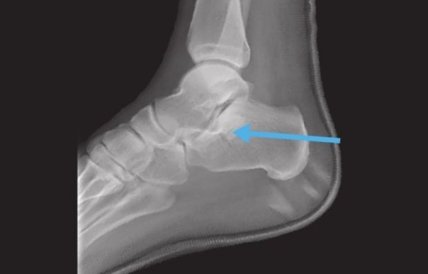

Серб упал со стены дома во время своего пребывания в Белграде. Йович сломал пяточную кость правой ноги, и на восстановление ему понадобится не менее трех месяцев.

Усик ответил на вызов борца Грицая

Бывший врач «Атлетико» Хосе Гонсалес пояснил: «Кость, которую сломал Йович, поддерживает весь вес тела и довольно устойчива к внешним воздействиям. В подавляющем большинстве случаев перелом возникает из-за очень сильной травмы или падения с большой высоты. Лечение изначально сводится к отдыху и физиотерапии. Если период реабилитации пойдет по плану, станет известно, как долго будет продолжаться восстановление».